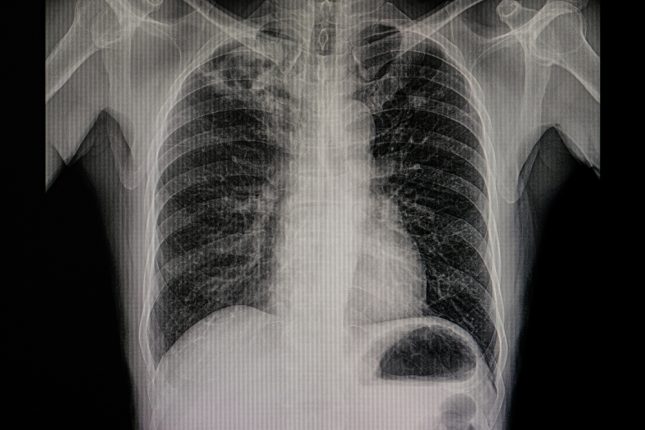

לייפת ריאתית

לייפת ריאתית מסיבה בלתי ידועה (Idiopathic Pulmonary Fibrosis – IPF) היא מחלת ריאה קטלנית שמאופיינת על ידי פגיעה באפיתל הריאה, פעילות מוגברת של תאים מסוג Myofibroblast ושיקוע של חומר חוץ תאי (Extracellular Matrix Deposition). שלפוחיות חוץ תאיות (Extracellular Vesicles – EVs) מבקרות את התקשורת הבין תאית על ידי נשיאה של מגוון מתווכי איתות, בכלל זה חלבוני WNTי– Wingless/Integrated) . חשיבות ה-EVs ב-IPF ומידת התרומה שלהם למחלה היא נושא שלא נחקר עד כה.